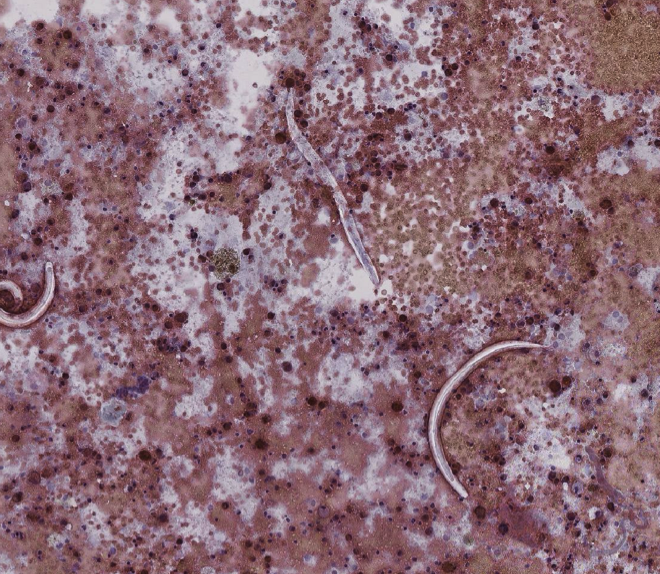

Caso Anquilostomiasis. Diagnóstico por lavado bronquioloalveolar

Caso clínico: Masculino 24 años VIH positivo, 9 días previos a su internamiento inició con dolor abdominal de tipo cólico, difuso, diarrea, astenia y adinamia